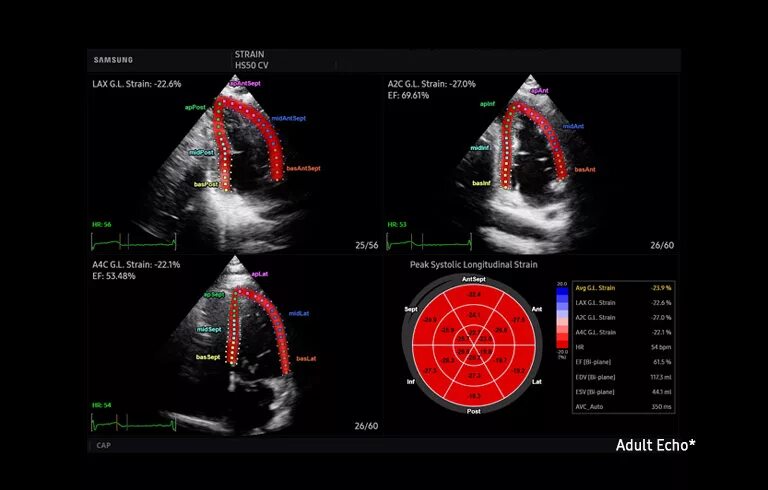

Системе hs